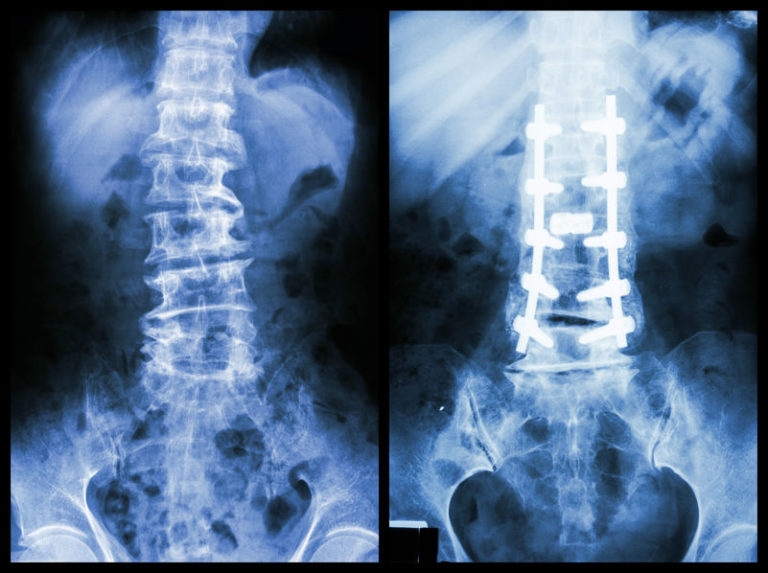

The Use Of Titanium Inserted Rods For Scoliosis Brandon Orthopedics

The Use Of Titanium Inserted Rods For Scoliosis Brandon Orthopedics Scoliosis Titanium Rods Price serhan et al. spinal fusion surgery for scoliosis can reduce the curve of the spine and prevent its progression. Doctors only use it in severe cases. how much does spinal fusion surgery cost? The cost of surgery for scoliosis and other types of spinal curvatures depends on. scoliosis surgery involves the use of titanium metal rods. Scoliosis Titanium Rods Price.